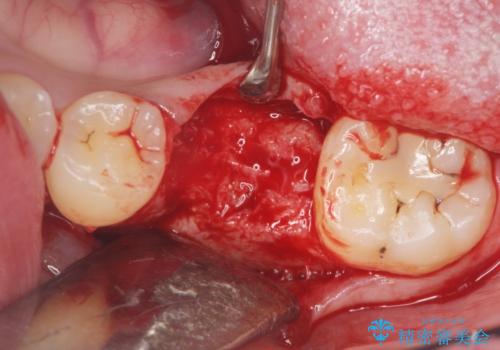

減ってしまった顎骨に増骨処置を行うことで、より安定した環境で長く使用できるようなインプラント治療を行っています。